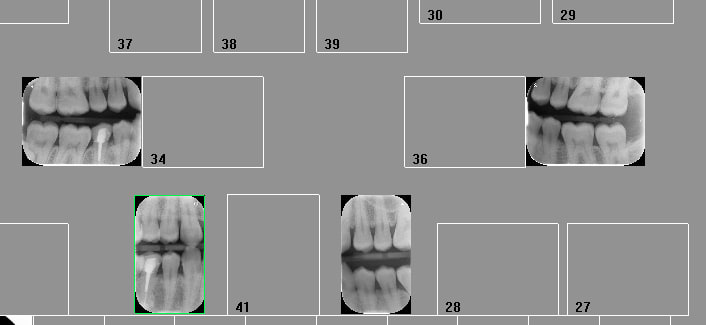

Je me suis rendu compte que certain compte 4 radios quand il prendre un bitewing de chaque cote.

Peut quelqu’un confirmer cela? Ça me pareil un peu contre intuitif mais si c’est la pratique valider je ferai comme tout le monde.

Bon pour revenir au sujet, un bitewing = un secteur=une radio.

Vous pouvez cotez autrement si ça vous chante, en sachant le risque d'indu que vous prenez !

On ne te parle pas d'un bite wing mais de 2. En général ça va par paire. -Tu dois pas en coter beaucoup car en général ils sont réalisé lors du premier RDV lors de la consult et tu ne peux pas les cumuler avec une consult : ils sont donc gratuits. Ou tu fais revenir le patient juste pour les faire ? -))

Et bin deux bitewing = deux secteurs = deux radios !!